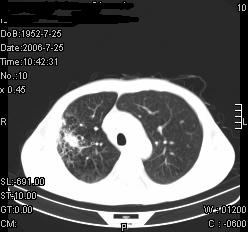

患者,男,54岁,咳嗦,咳痰20天。抗炎治疗2周。现esr76mm/h,目前患者症状明显好转,但发现两次ct片未见明显变化。两次分别做与7.25、7.31。第一次诊断右肺上叶炎症累计胸膜。大家看,从影像上内排除结核吗?

结核的可能性非常大,右上肺病变应该考虑干酪性肺炎。理由:

3.虽经抗炎治疗肺窗病灶有所吸收、减小,但纵隔窗病灶形态、密度、范围无明显变化。如果是单纯的大叶性肺炎,“抗炎治疗2周,目前患者症状明显好转”病灶应该基本消散了,至少也处于吸收消散期,密度变淡、范围变小。同时本病例所示其内的密度不均匀,见多发大小不一空洞样影也不符合大叶性肺炎吸收消散期表现。

病灶特点:片状 索条 结节混杂影,部分融合,密度不均,广泛累及相应胸膜.

临床治疗;二周未吸收.但症状好转.

多考虑:肺结核.